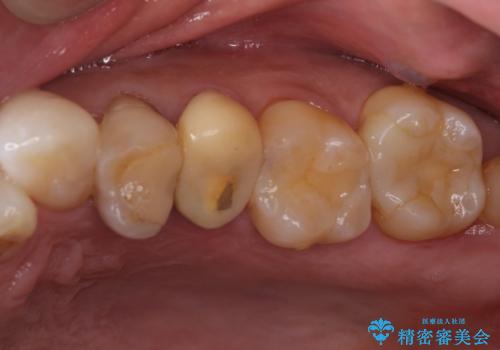

左上の仮歯を2年使用して穴があいて外れたことをきっかけにご来院されました。

レントゲン上からも、歯の中(根管)が汚れている可能性があることをご説明したところ、根管治療からやり直しをすることになりました。

- 2年ほど放置していた左上の仮歯がとれたことをきっかけにご来院された患者様です。

セラミック治療がご希望でしたが、ときどき歯肉が腫れるということで根管治療もご希望されました。